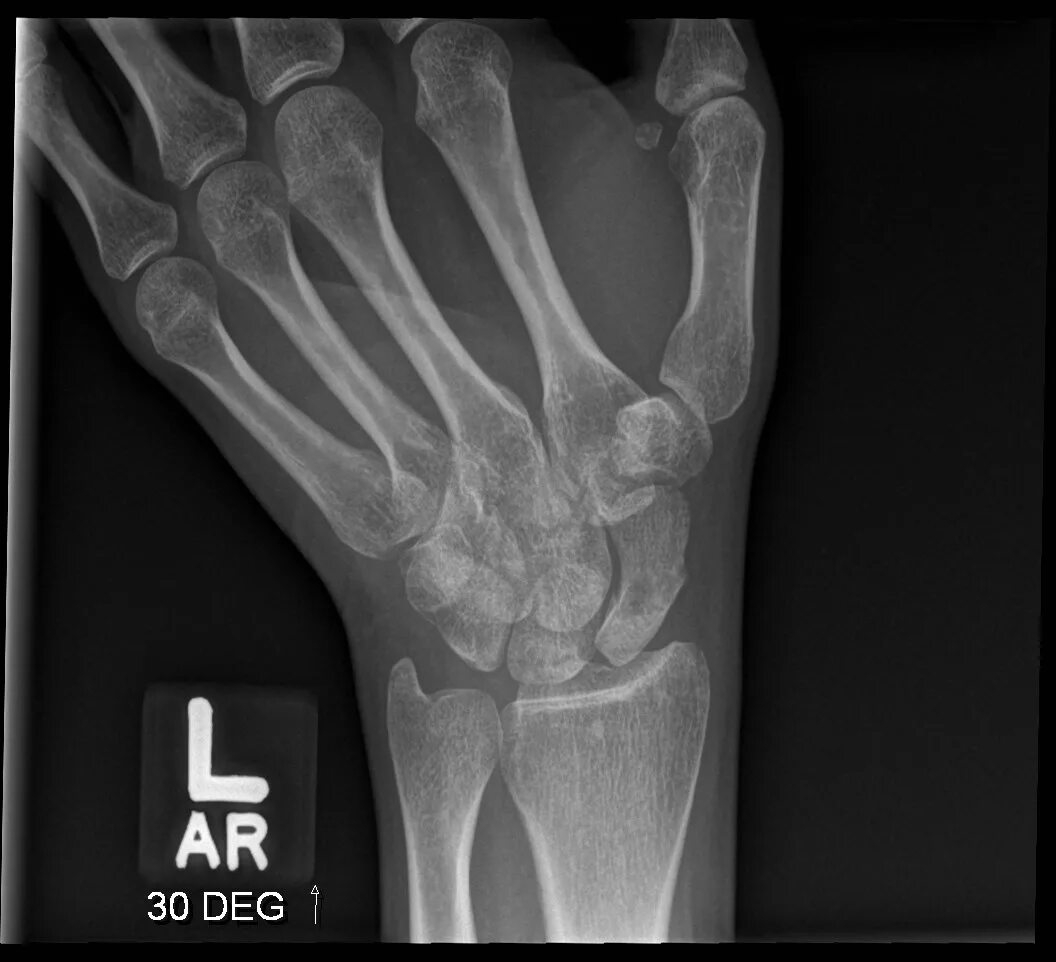

Source x rays